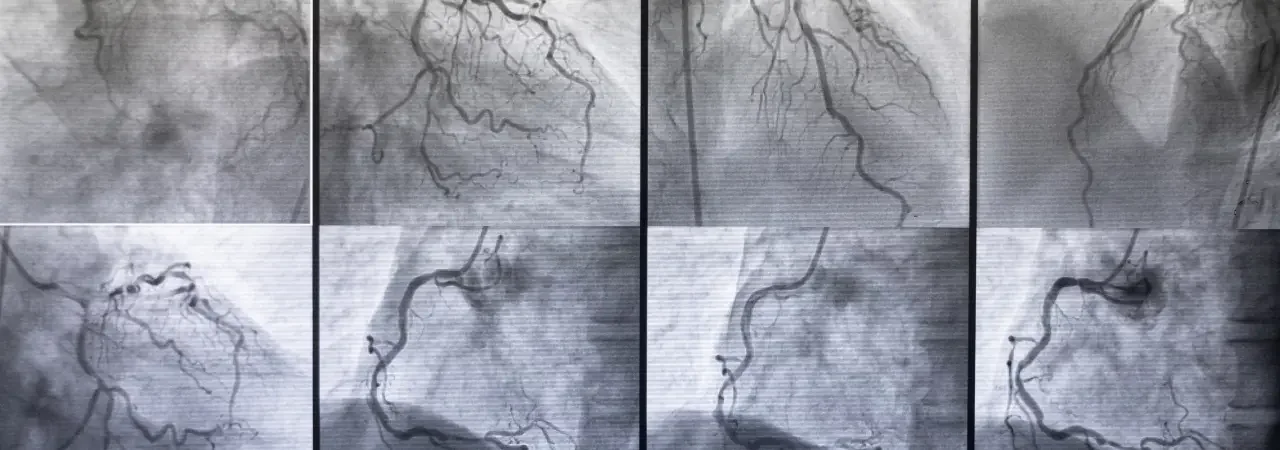

Giriş yolu seçimi (femoral/iliyak) ve damar hazırlığı

Önce, CTA ile ölçümleri teyit eder; femoral ya da iliyak girişi planlarız. Ultrason eşliğinde ponksiyon yapar, kılavuz tel ve kılıfı yerleştiririz. Heparinizasyon dozunu ağırlığa göre uygular, basınçlı yıkama ve hava boşaltma prosedürleriyle seti hazırlarız. Ardından, referans işaretleri için pigtail kateterle aortografiyi gerçekleştirir, iniş ve çıkış zonlarını işaretleriz. İhtiyaç halinde pre-dilatasyon yaparız. Bu adımlar, akışın sorunsuz ilerlemesi için kritiktir.

Stent greft implantasyonu, görüntüleme ile doğrulama ve final kontrol

Sonrasında, planlanan konfigürasyonda tevar stent greft yerleştiririz. Floroskopi ve road-map ile doğru seviyeyi hizalar, solunum-apne ve tansiyon kontrolü altında grefti açarız. Gerekirse post-dilatasyon balonlama yaparız. Nihai aortografiyle sızdırmazlığı (endo-lik) kontrol eder, visseral ve iliak akımın korunduğunu doğrularız. Son olarak kapama cihazlarıyla kanülasyon yerini güvenceye alırız ve hemodinamik-stent pozisyon takibini başlatırız. Bu sistematik yaklaşım, endovasküler aort tedavisi başarısını artırır.